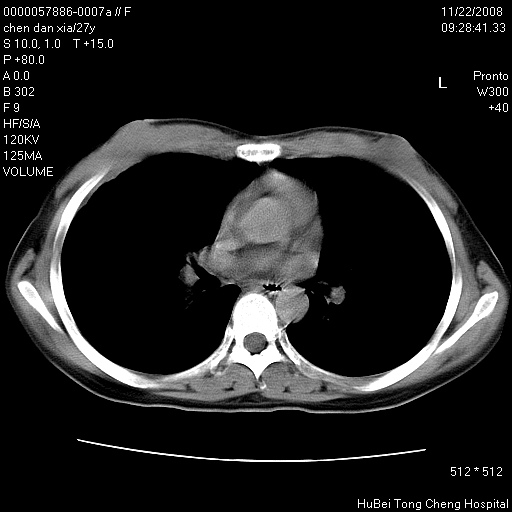

标题: CT16752:F,27Y。发热咳嗽20余天,伴盗汗。 [打印本页]

标题: CT16752:F,27Y。发热咳嗽20余天,伴盗汗。

考虑双肺粟粒性肺tb,右侧胸膜增厚.

右下肺见片絮状影,两肺野内分布不均的小结节影,结核并肺内播散可能性大,建议结合实验室检查 .

右下肺纹理模糊;纵隔可见肿大淋巴节;右心缘旁结节,边缘光滑,纵隔窗病变范围较肺窗明显小,首先考虑右下肺结核,不排外淋巴瘤

右侧前胸壁胸膜局限性肥厚(胸膜炎?)其他的强化观察.

下肺结节,结节内钙化,肺门纵隔淋巴肿大 结核可能性大

好像有微结节,建议薄层以除外结核